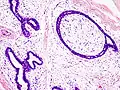

| Histopathologic image of breast fibroadenoma. Core needle biopsy. H&E stain. | |

Fibroadenoma of the breast is a benign tumor composed of a biplastic proliferation of both stromal and epithelial components.[12][13] This biplasia can be arranged in two growth patterns: pericanalicular (stromal proliferation around epithelial structures) and intracanalicular (stromal proliferation compressing the epithelial structures into slit-like spaces).

These tumors characteristically display hypovascular stroma compared to malignant neoplasms.[2][14][9] Furthermore, the epithelial proliferation appears in a single terminal ductal unit and describes duct-like spaces surrounded by a fibroblastic stroma. The basement membrane is intact.[15]

Fibroadenoma histology (H&E). The image demonstrates intracanalicular morphology (bottom left) and pericanalicular morphology (top right)

Histopathologic image of breast fibroadenoma. Core needle biopsy. Hematoxylin & eosin stain.

Histopathologic image of breast fibroadenoma showing proliferation of intralobular stroma compressing and distorting the epithelium. H&E stain.